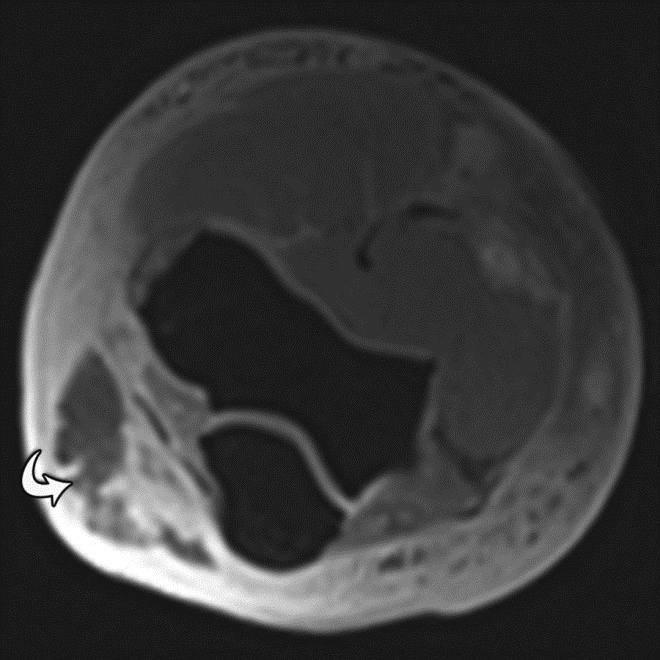

Repetitive, periodic motion can also occur due to cardiac activity or vascular pulsation and result in ghost images propagating along the phase-encoding direction (Peh, 2001). Pulsatile motion amplitude and speed will determine the brightness of this artifact (Wood, 1985). Cardiac or respiratory gating, as well as use of short acquisition times, may be used to minimize the effects of this periodic motion artifact; however, these artifacts are more problematic in cardiac and abdominal MR imaging than in musculoskeletal MR imaging (Singh, 2014). Pulsation artifact from the popliteal artery is a common manifestation of this artifact in musculoskeletal imaging, and may result in obscuration of the menisci (Figure 16).

Pulsation Artifact. Axial T2-weighted fat-saturated MR image of the pelvis demonstrates femoral artery pulsation resulting in ghost images (arrowheads) obscuring the anterior labra and simulating femoral head lesions bilaterally.